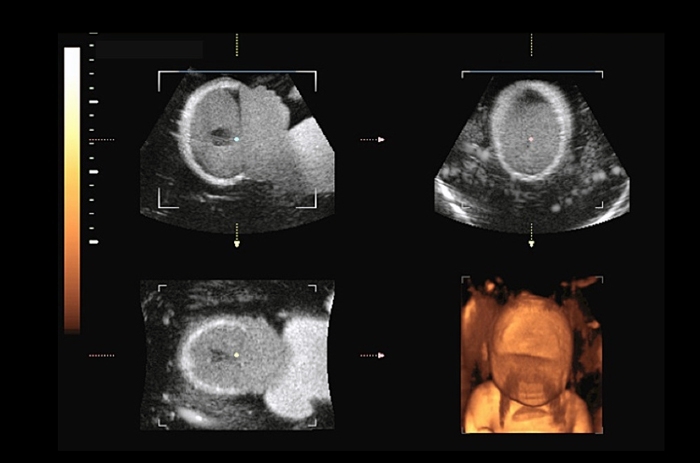

Fetal Ultrasound Biometrics Phantom

- Demonstrate system capabilities

- Teach imaging protocols to estimate gestational age

- Practice 2D, 3D & 4D fetal scan techniques

- Measure CRL, BPD, FL and AC

Fetal Ultrasound Training Phantom

- Demonstrate system capabilities

- Teach imaging protocols to estimate gestational age

- Practice 2D, 3D & 4D fetal scan techniques

Dimension |

35 cm x 17 cm x 17 cm |

Weight |

8.9 kg (24 lbs.) |

Targeted Biometric Dimensions |

BPD: 4.2 cm (10th percentile) |

Materials |

Housing: PVC, Vinyl & ABS |

Dimensions |

41 cm x 23 cm x 23 cm |

Weight |

15.8 kg (42 lbs.) |

Housing Material |

PVC, ABS & Vinyl |

Phantom Material |

Proprietary Gels |

Background Gel |

Attenuation: <0.10 dB/cm-MHz |

Fetal Soft Tissue |

Attenuation: 0.55 dB/cm-MHz |

Field of View |

20 cm x 30 cm x 180°C |